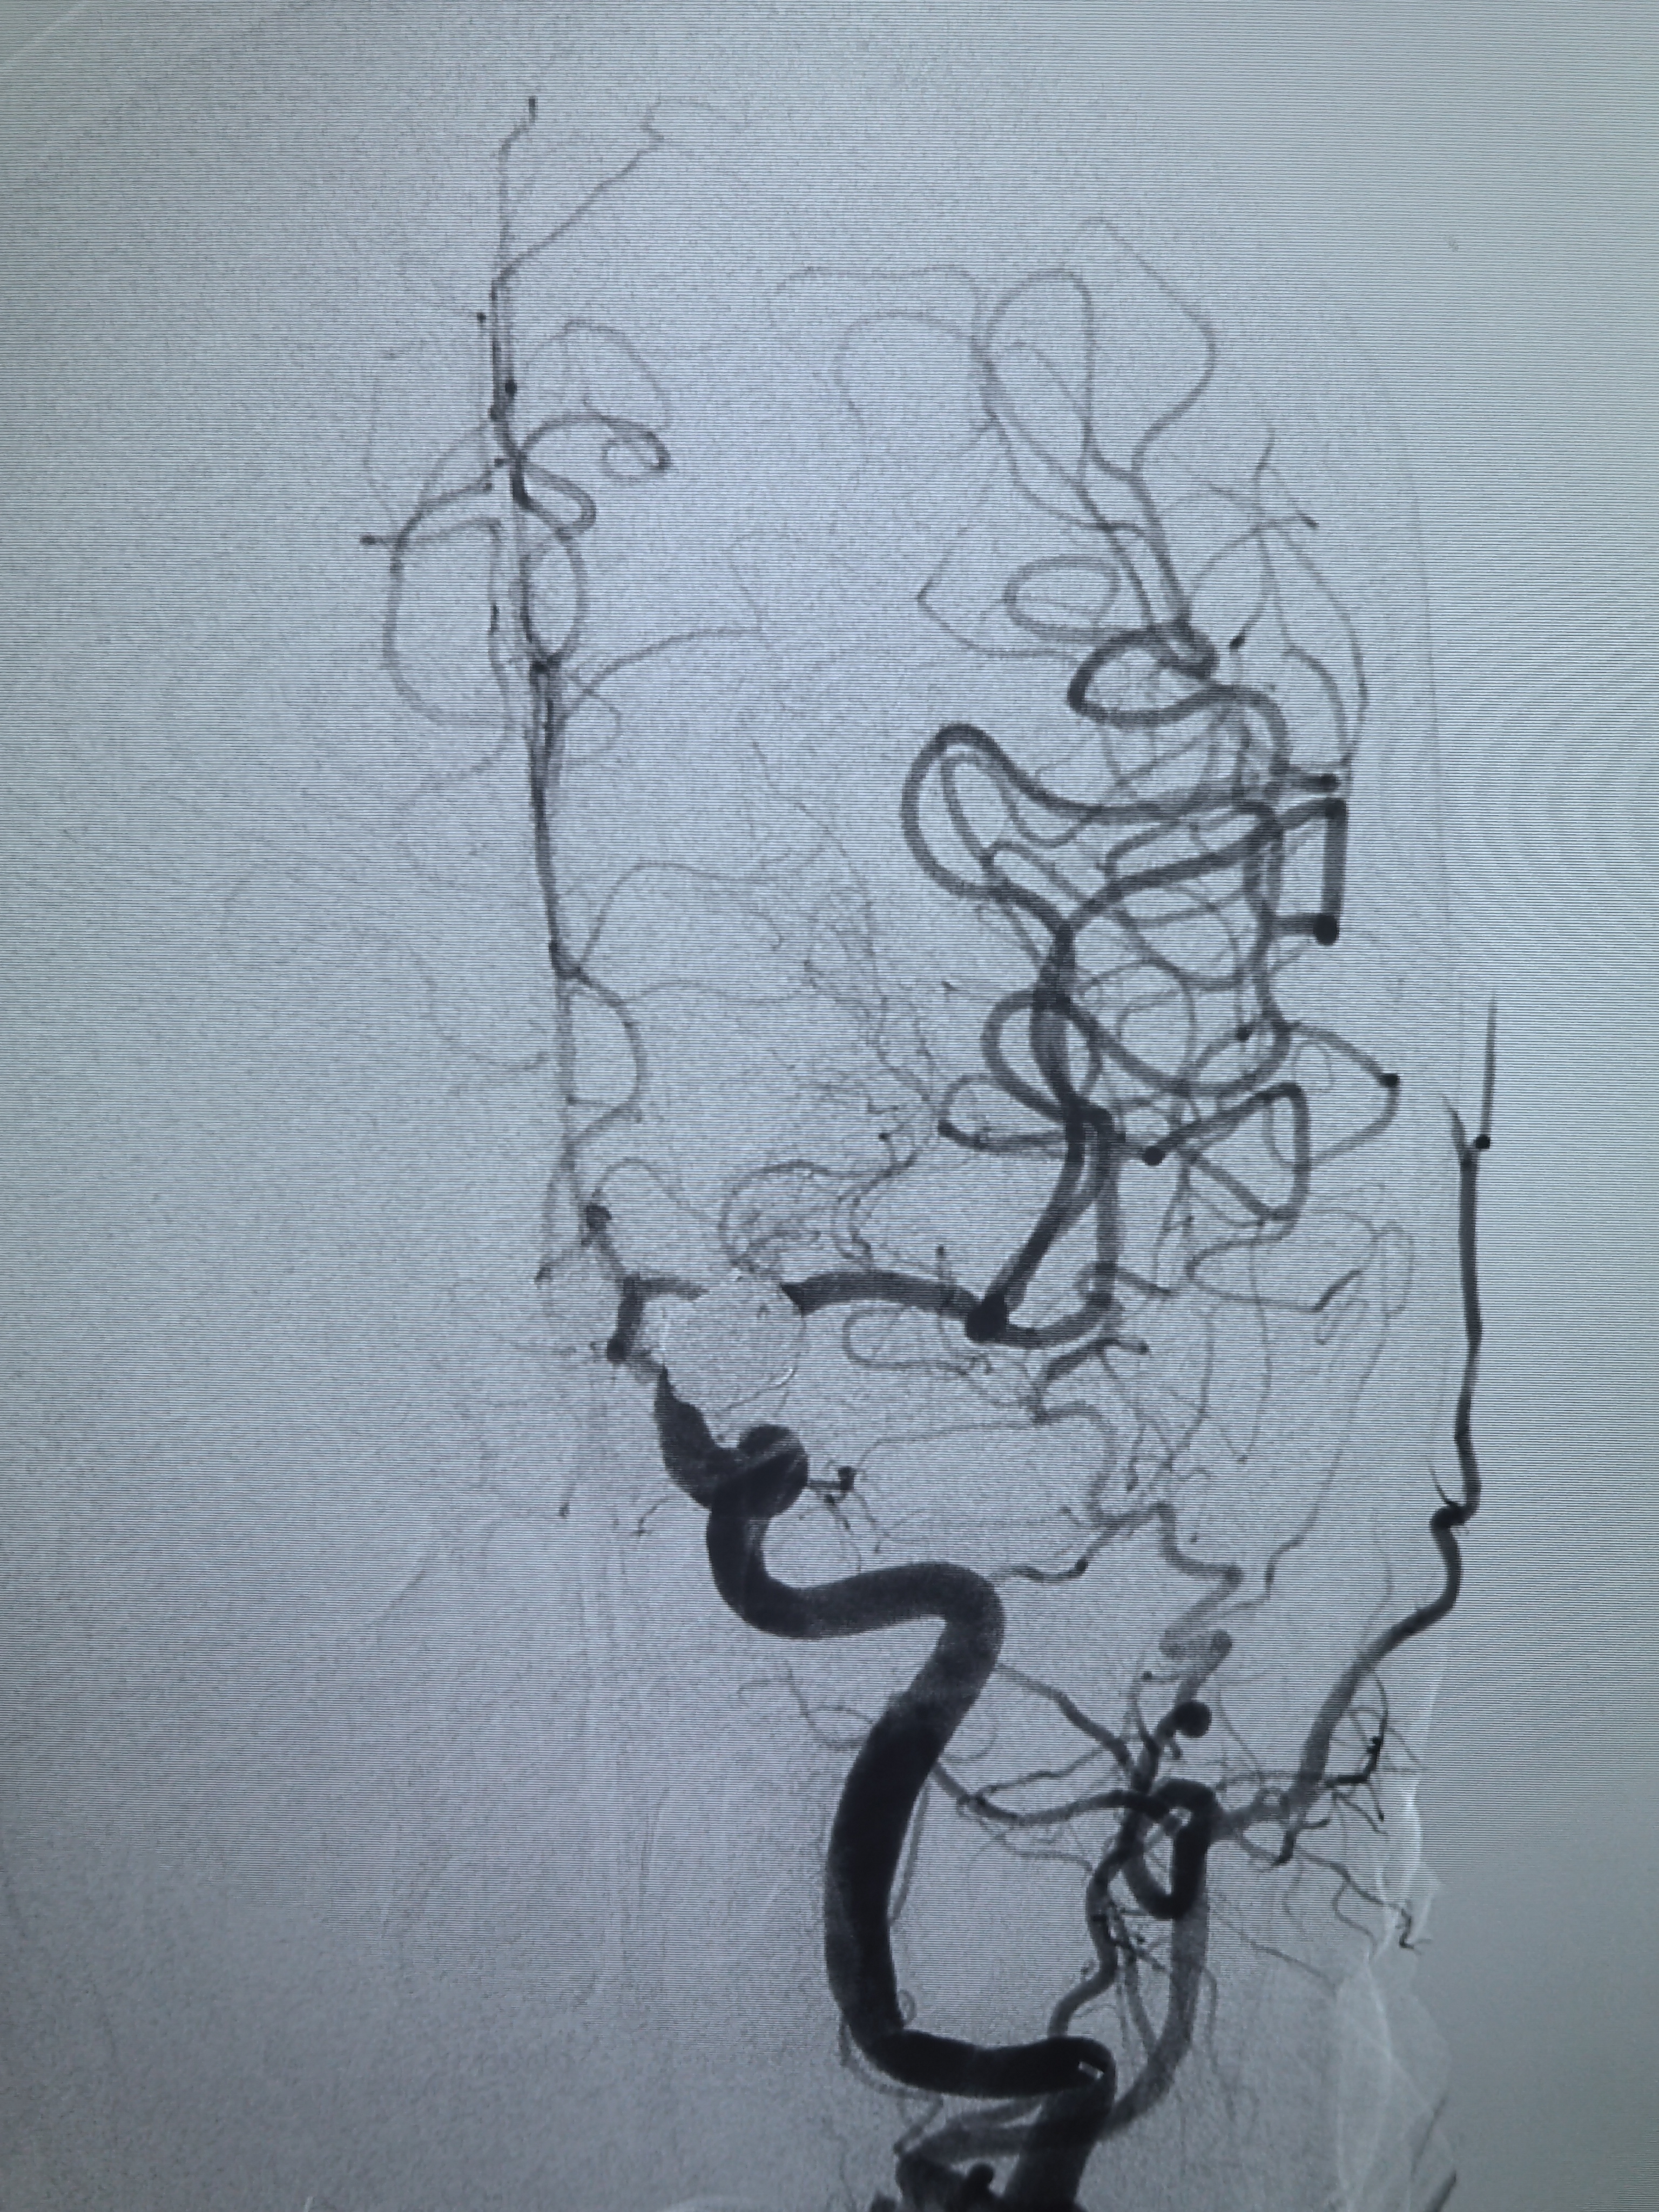

工作位造影!

椎基底动脉造影无P1!

压颈试验显示同侧P1,手术难度降低,不用考虑保护胚胎型大脑后动脉瘤了!